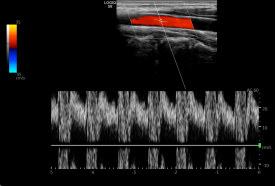

" x% S# p8 r3 n+ G. j 取样线角度校正(Angle Correct) 9 U1 o# L, h: M' N% ]9 Q) c

根据多普勒公式:fd=2Vcosθf0/c 即:V=fd c/2f0cosθ。对一个给定的反射体速度,多普勒角度θ显著影响探测到的频移。当血流方向朝向探头,θ为0度,cosθ为1。当血流方向垂直于探头,θ为90度,cosθ为0,就检测不到多普勒频移。在实际应用中,常使探头声束与动脉之间的角度呈30度— 60度之间(心脏检查时小于30度),这个角度可以探测到可靠更准确误差更小的多普勒信号。